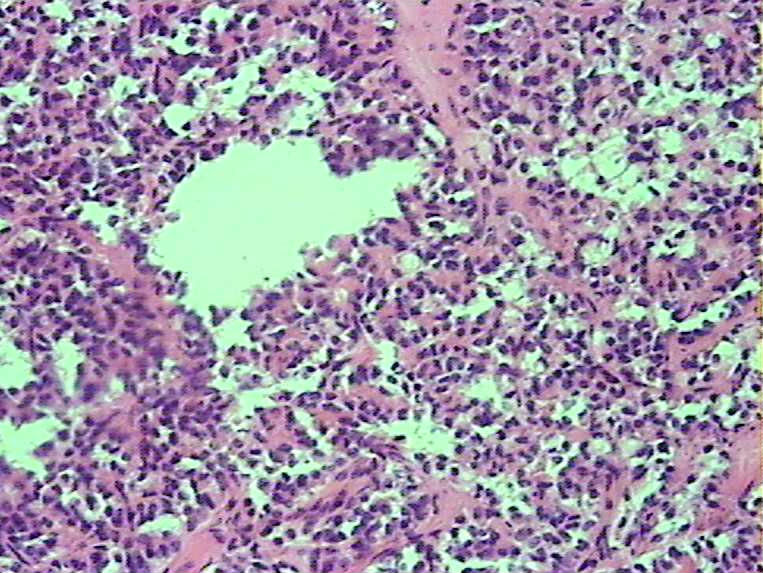

胰腺肿物 大体:灰白色肿物一枚大小:3*2*2cm,切面实性,质中。女,52

胰腺实性-假乳头状瘤